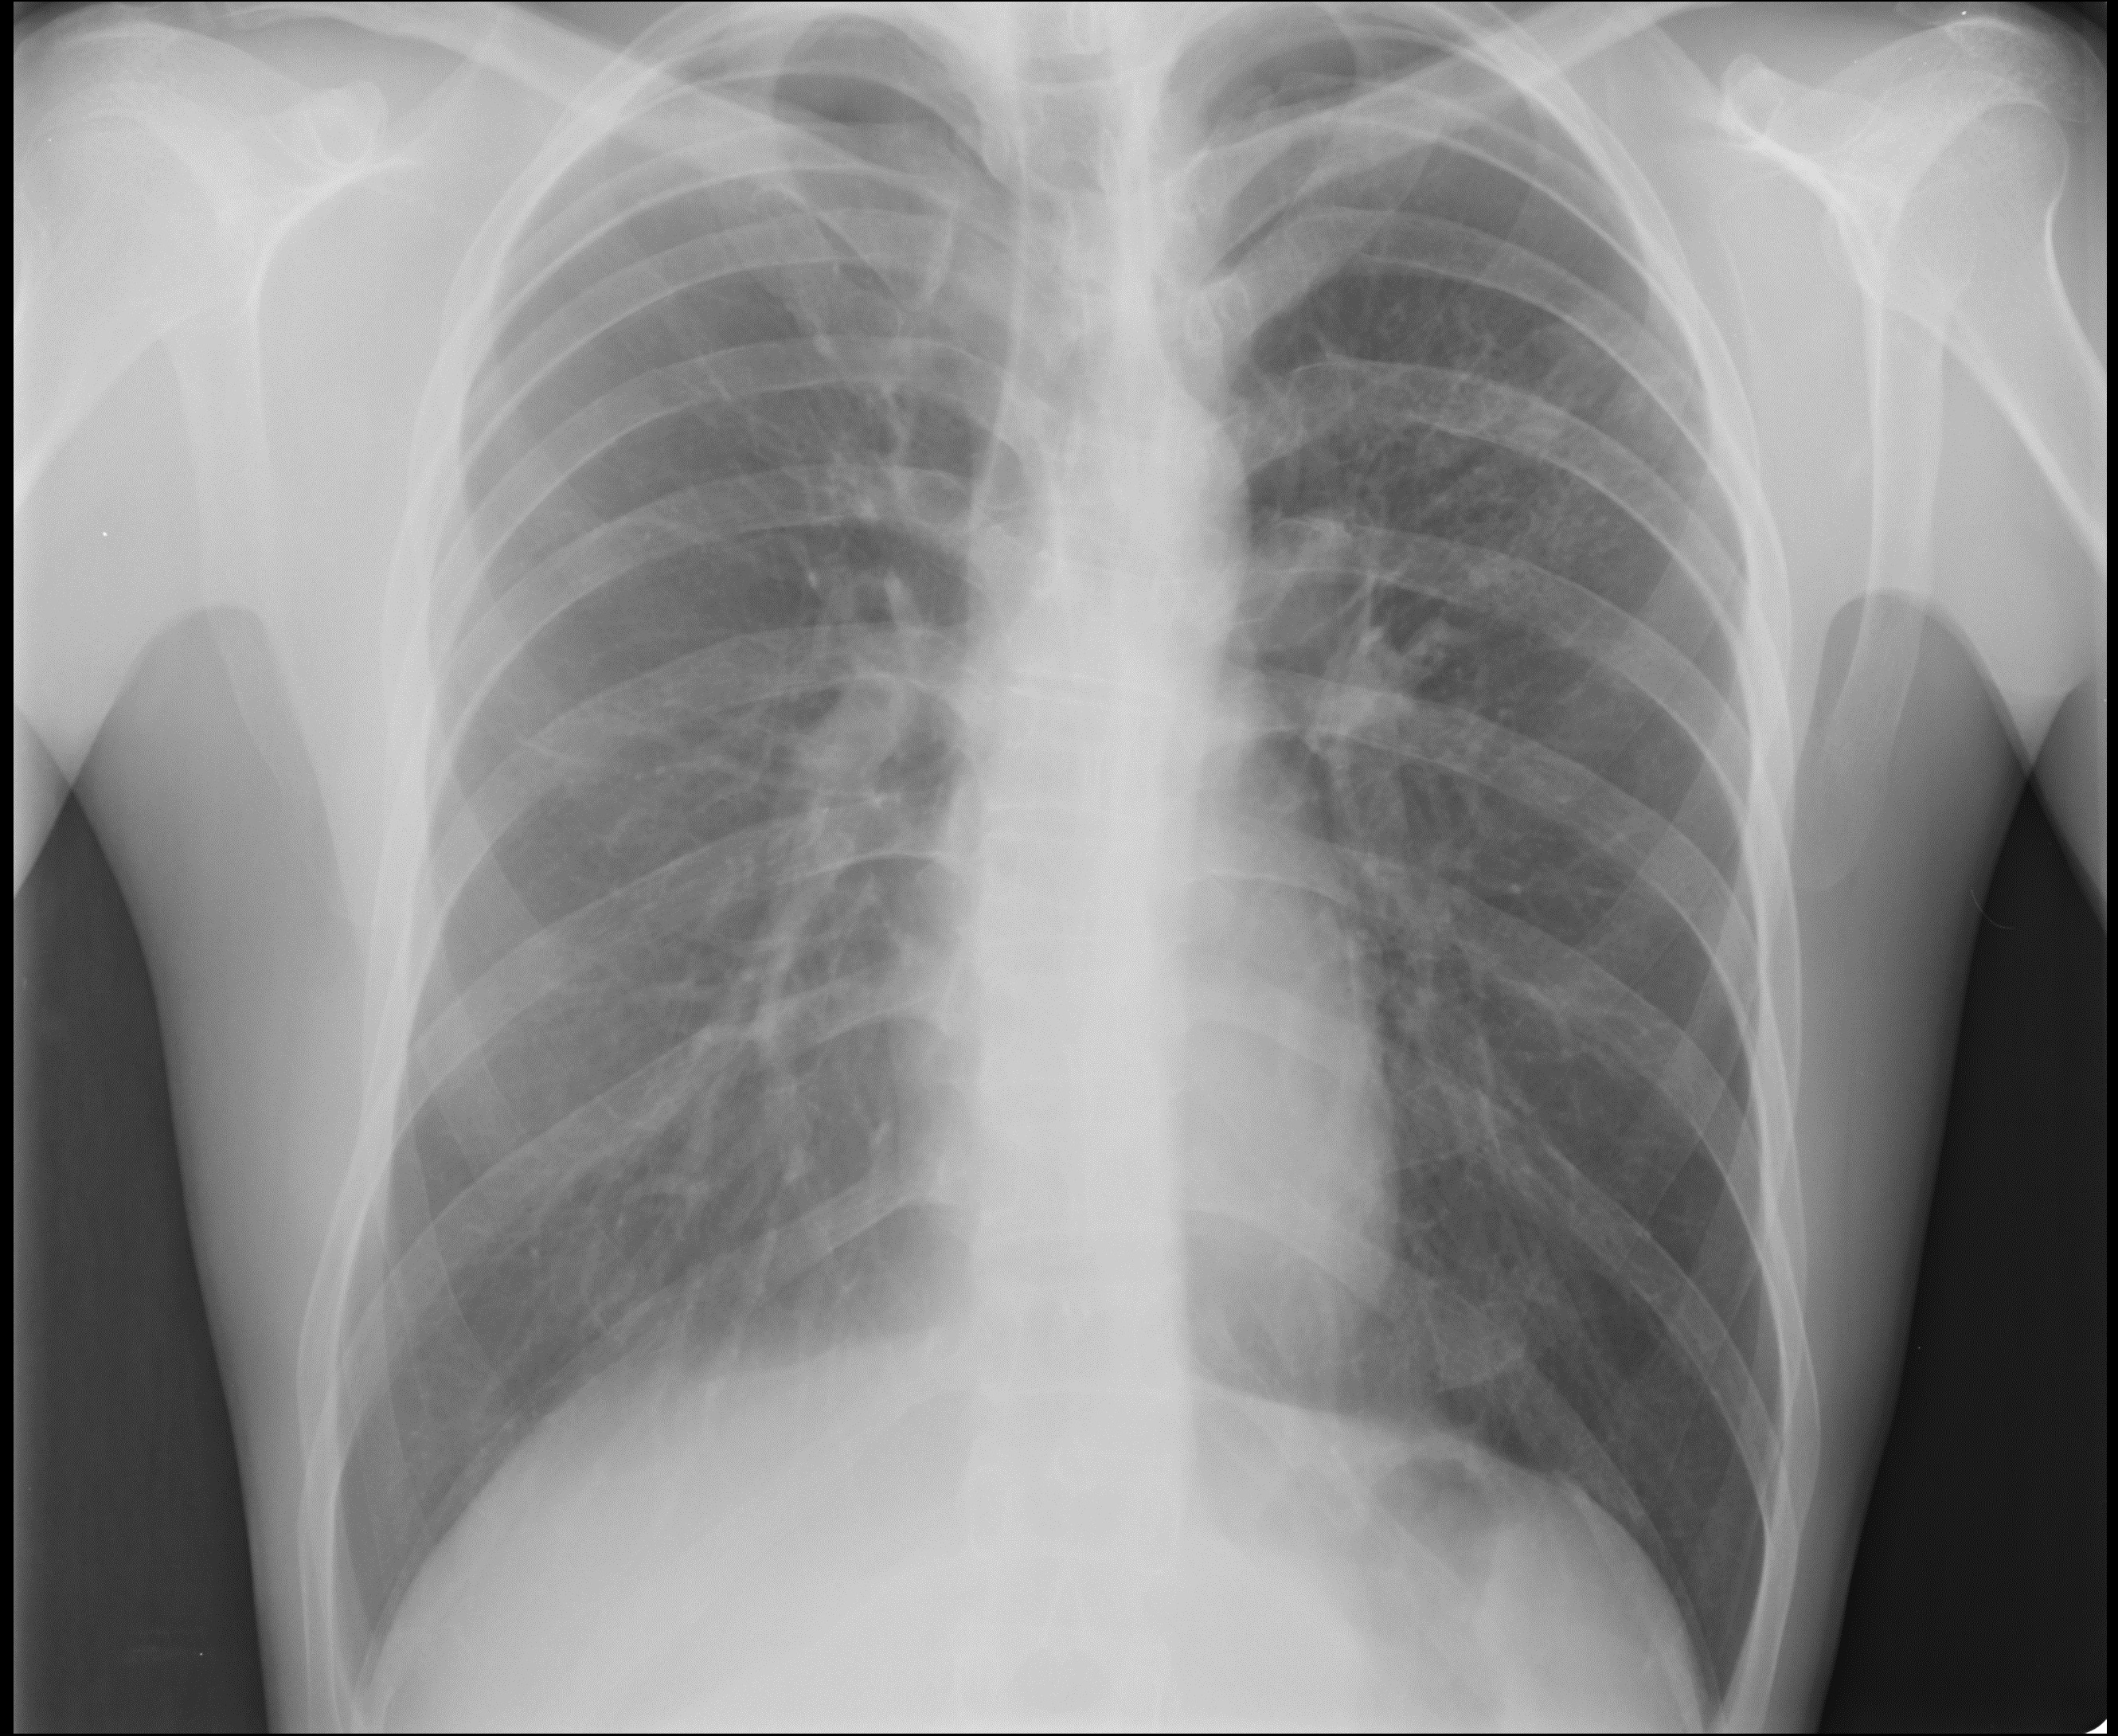

Снимок легких при туберкулезе является важным методом диагностики этого заболевания. На рентгеновских снимках можно увидеть изменения в легких, которые свойственны туберкулезу.

Фотографии снимков легких при туберкулезе

В данной статье представлены многочисленные фотографии снимков легких при туберкулезе, чтобы помочь вам понять, как выглядят изменения легких на рентгеновских снимках при этом заболевании.